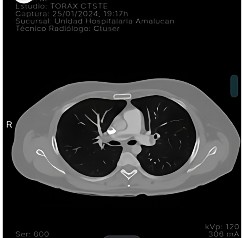

La sintomatología inició con un dolor precordial opresivo, que el paciente calificó como 10/10 en la escala visual análoga (EVA), el cual se veía exacerbado a la inspiración profunda, sin atenuantes ni irradiaciones. Posteriormente, presentó disnea ante pequeños esfuerzos y síncope de un minuto de duración, caída de su propia altura y contusión en la rodilla y el cráneo. Ingresó al hospital general de la zona con dolor precordial y pulsioximetría al 85 %. El electrocardiograma (EKG) evidenció taquicardia sinusal (122 lpm) y patrón de McGinn-White (S1-Q3-T3) (Figura 1). La serología reportó dímero D 1795 µg/dl, CPK 113 mg/dl, CPK MB 17,1 mg/dl. La angiotomografía evidenció tromboembolia pulmonar en las ramas principales, segmentarias y subsegmentarias (Figura 2). Se inició tratamiento de anticoagulación con enoxaparina y se refirió al paciente a unidad terciaria.

Figura 2 Angiotomografía: presencia de trombo en la bifurcación de los grandes vasos pulmonares